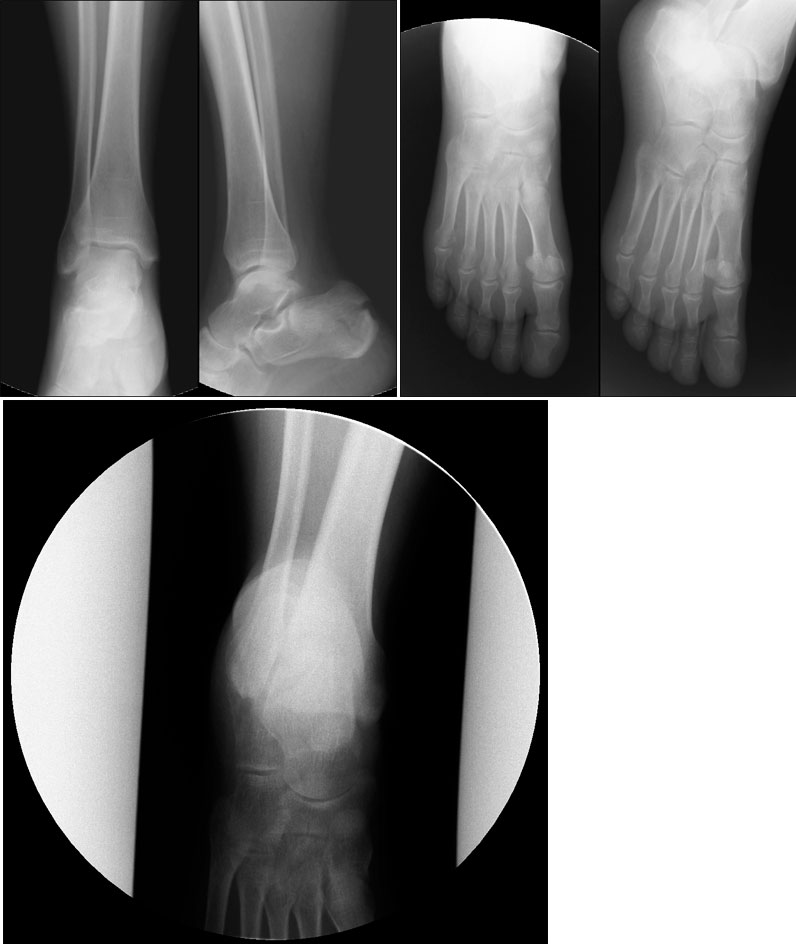

Женщина, возраст 55 лет.,вес 60кг.11.11.13 Падение с высоты 3х метров на ногу. сильная гематома на внутренней и внешней поверхности стопы. При первичном осмотре в республиканской больнице (г.Сухум) установлен диагноз: ушиб. Пациент отпущен домой.28.11.13 Сильные боли в течение двух недель.Сделан повторный рентген. Гематома спала, но полностью не рассосалась, боли уменьшились. Вторичный осмотр в военном госпитале (г.Агудзера).Диагноз: Осколочный перелом пятки со смещением.Лечение: Наложен гипс.Снимки прилагаю. Прошу помощь, по возможности, определить точность диагноза и лечения. Спасибо.

Снимок №1

Снимок №2

Снимок №3

Снимок 1,2,3.

Перелом пятки. Если есть возможность сделать малоинвазивный остоетсоинтез - то сделать, если нет - можно и консервативное, результат должен быть удовлетворительный.